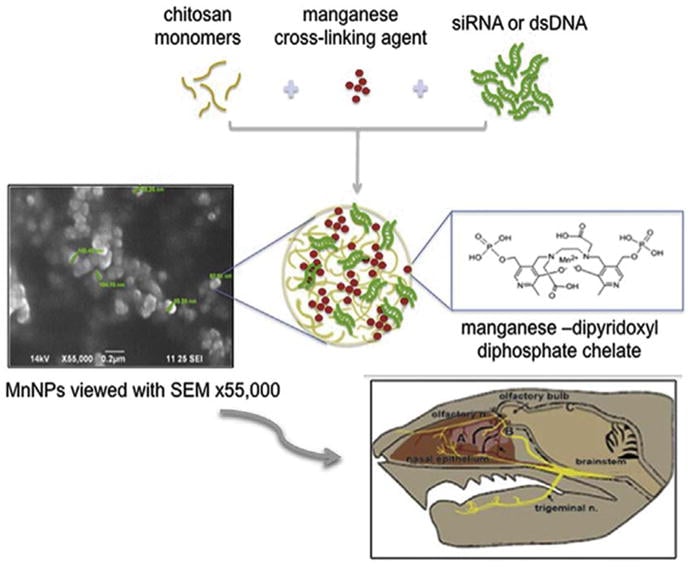

NOVEMBER 21, 2017, New publication from the Aronin & Khvorova labs. Chitosan-Mangafodipir nanoparticles designed for the intranasal delivery of siRNA and DNA to the brain. Sanchez-Ramos J, Song S, Kong X, Foroutan P, Martinez G, Dominguez-Viqueria W, Mohapatra S, Mohapatra S, Haraszti RA, Khvorova A, Aronin N, Sava V. J Drug Deliv Sci Technol. 2018 Feb;43:453-460. doi: 10.1016/j.jddst.2017.11.013. Epub 2017 Nov 21.

NOVEMBER 21, 2017, New publication from the Aronin & Khvorova labs. Chitosan-Mangafodipir nanoparticles designed for the intranasal delivery of siRNA and DNA to the brain. Sanchez-Ramos J, Song S, Kong X, Foroutan P, Martinez G, Dominguez-Viqueria W, Mohapatra S, Mohapatra S, Haraszti RA, Khvorova A, Aronin N, Sava V. J Drug Deliv Sci Technol. 2018 Feb;43:453-460. doi: 10.1016/j.jddst.2017.11.013. Epub 2017 Nov 21.